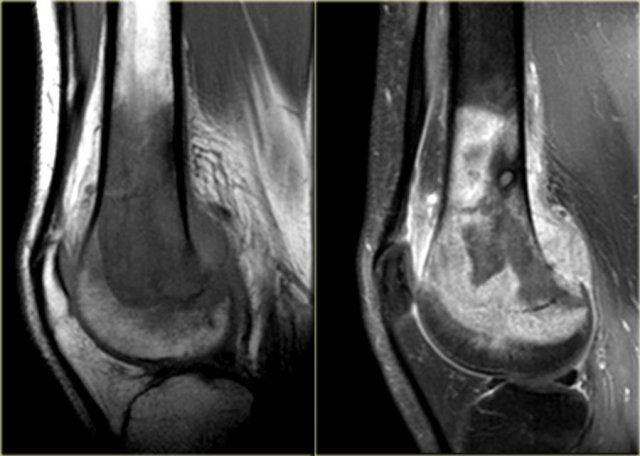

Đây là tổn thương nằm ở vùng đầu xương và hành xương của đầu trên xương cánh tay.

Tổn thương chủ yếu bị vôi hóa.

Hình ảnh T1W mặt phẳng vành tai cho thấy bờ tổn thương có dạng thùy và tín hiệu thấp ở ngoại vi do các vôi hóa.